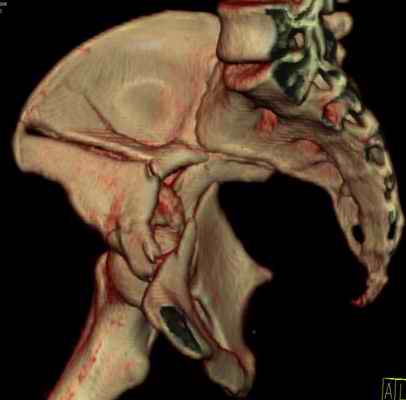

Посылаю схемы и 3D реконструкцию подобного повреждения. Называется он полным высоким двухколонным переломом вертлужной впадины, а "переломы крыла и тела подвздошной кости" входят в это понятие.

Вариантов остеосинтеза много (можно и не оперировть, т.к. конгруентность при таких переломах как правило сохраняется)

1 закрытая репозиция аппаратом + фиксация через проколы винтами

2 закрытая репозиция передней колонны + открытая задней колонны из задне-неружного доступа

3 открытая репозиция передней колонны из подвздошнго доступа + открытая задней колонны из задне-наружного доступа

4 открытая репозиция из илиоингвинального доступа

5 открытая репозиция из Y образного доступа

Я бы ориентировался на Y образный доступ

или из двух если есть сомнения в целостности задних отделов крыла.

прикладываю схему доступа и случай.

Одним задне наружным переднюю колонну не достать, а илио-ингвинальный более сложный не позволяет контролировать суставную поверхность и трудно управлять задней колонной.